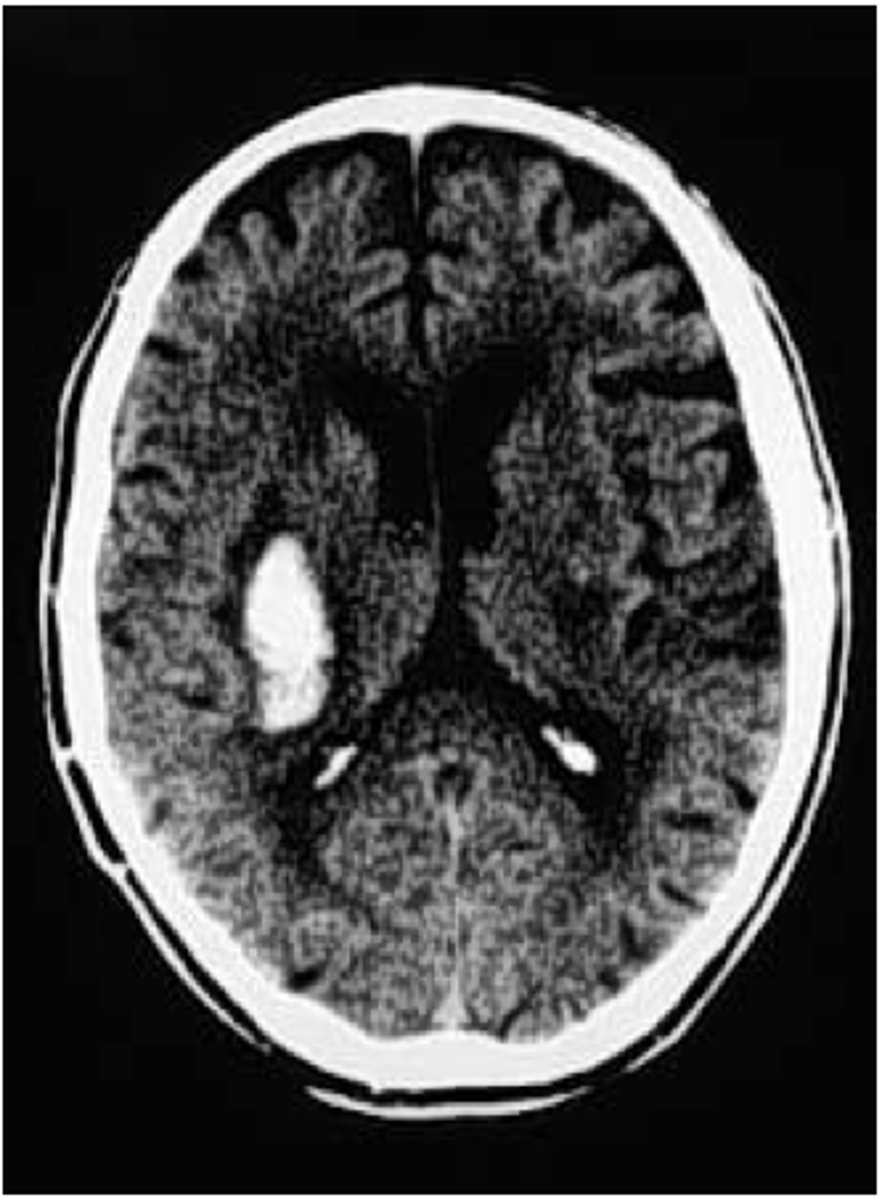

intracranial hemorrhage (ICH)

bleeding within the skull that leads to increased ICP and reduced cerebral perfusion

*traumatic or spontaneous

*major cause for neurologic morbidity and mortality

intracerebral hemorrhage

bleeding within the brain tissue

ICH

presentation of what impairment/issues with what cranial structure?

- headache

- nausea/vomiting

- altered consciousness

- weakness

- speech or vision deficits

- seizures

- rapid neurological decline